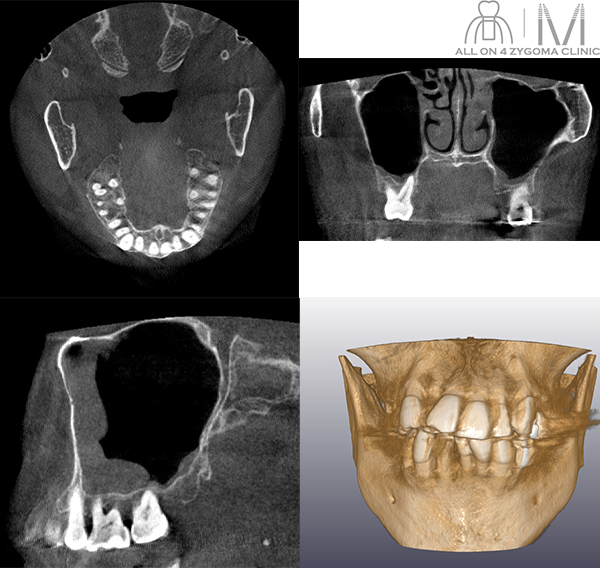

術前CT画像所見